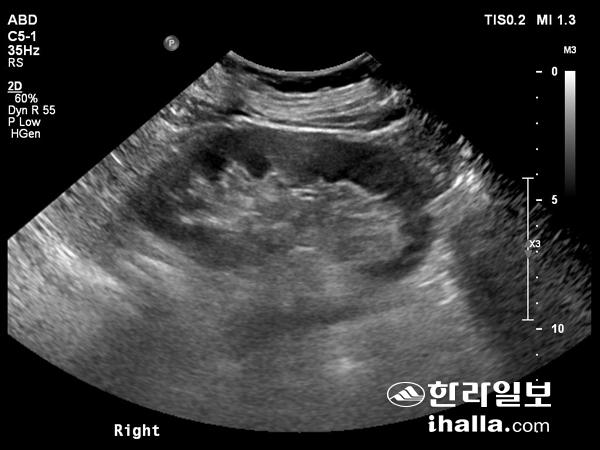

간 초음파.

건강검진이나 만성 간염 환자에서 간경변으로의 이행여부와 간암의 발생 등을 보기 위해 시행하는게 복부 초음파이다. 대개 검진시 대부분 시행하기 때문에 누구나 알고 있는 검사항목이기도 하다. 제주대학교병원 영상의학과 이정섭 교수의 도움으로 복부 초음파에 대해 자세히 알아본다.

간, 담낭, 담관, 췌장 등을 검사하는 상복부 초음파의 경우 주로 상복부 통증 혹은 지속적인 소화 불량, 우측 혹은 좌측 갈비뼈 아래에서 간 혹은 비장이 크게 촉진될 때, 간 기능검사에서 이상 소견이 있을 때, 혈액 검사에서 간암 수치나 췌장암 수치가 상승했을 때, 간염, 간경변증, 지방간 환자들의 정기적인 추적 검사, 양성 간 종양, 담낭 용종, 양성 췌장 종양 등의 정기적인 추적검사, 그 외에 건강검진을 위해 시행하고 있다.

초음파 영상을 실시간으로 보면서 간종양, 간실질, 췌장종양 등에 대해 조직검사를 할 수도 있고, 초음파 유도 하에 작은 간암에 대해 고주파열치료 같은 치료를 시행할 수도 있다. 비뇨기계 초음파의 경우 혈뇨, 옆구리 통증, 신기능 이상 등에 대한 원인 감별을 위해 시행하고, 신낭종이나 신결석 등의 추적 관찰에도 이용한다. 우하복부 통증의 경우 응급수술을 요하는 질환인 충수돌기염을 배제하기 위해 충수돌기 초음파를 시행하고, 하복부 통증 역시 소장 및 대장 초음파를 통해 원인을 찾아 볼 수 있다.